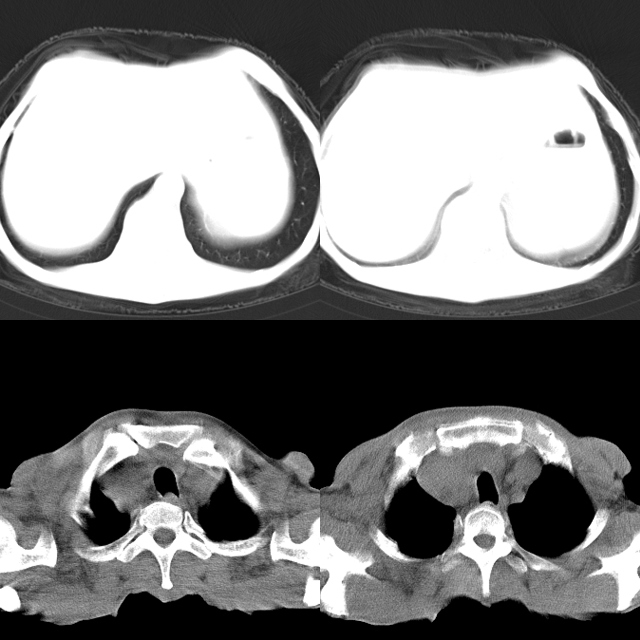

以下是引用心路寻觅在2010-4-17 18:35:00的发言:[br]纵膈多组淋巴结肿大呈“冰冻纵膈”,左肺上叶空洞伴其内结节密度影,考虑淋巴瘤伴左肺上叶曲霉菌感染。[br][br][本贴已被 心路寻觅 于 2010-4-17 18:36:23 修改过]

以下是引用zhangzhongshou在2010-4-17 19:32:00的发言:[br]一元论考虑左肺空洞型肺癌并纵隔淋巴结转移可能性大。